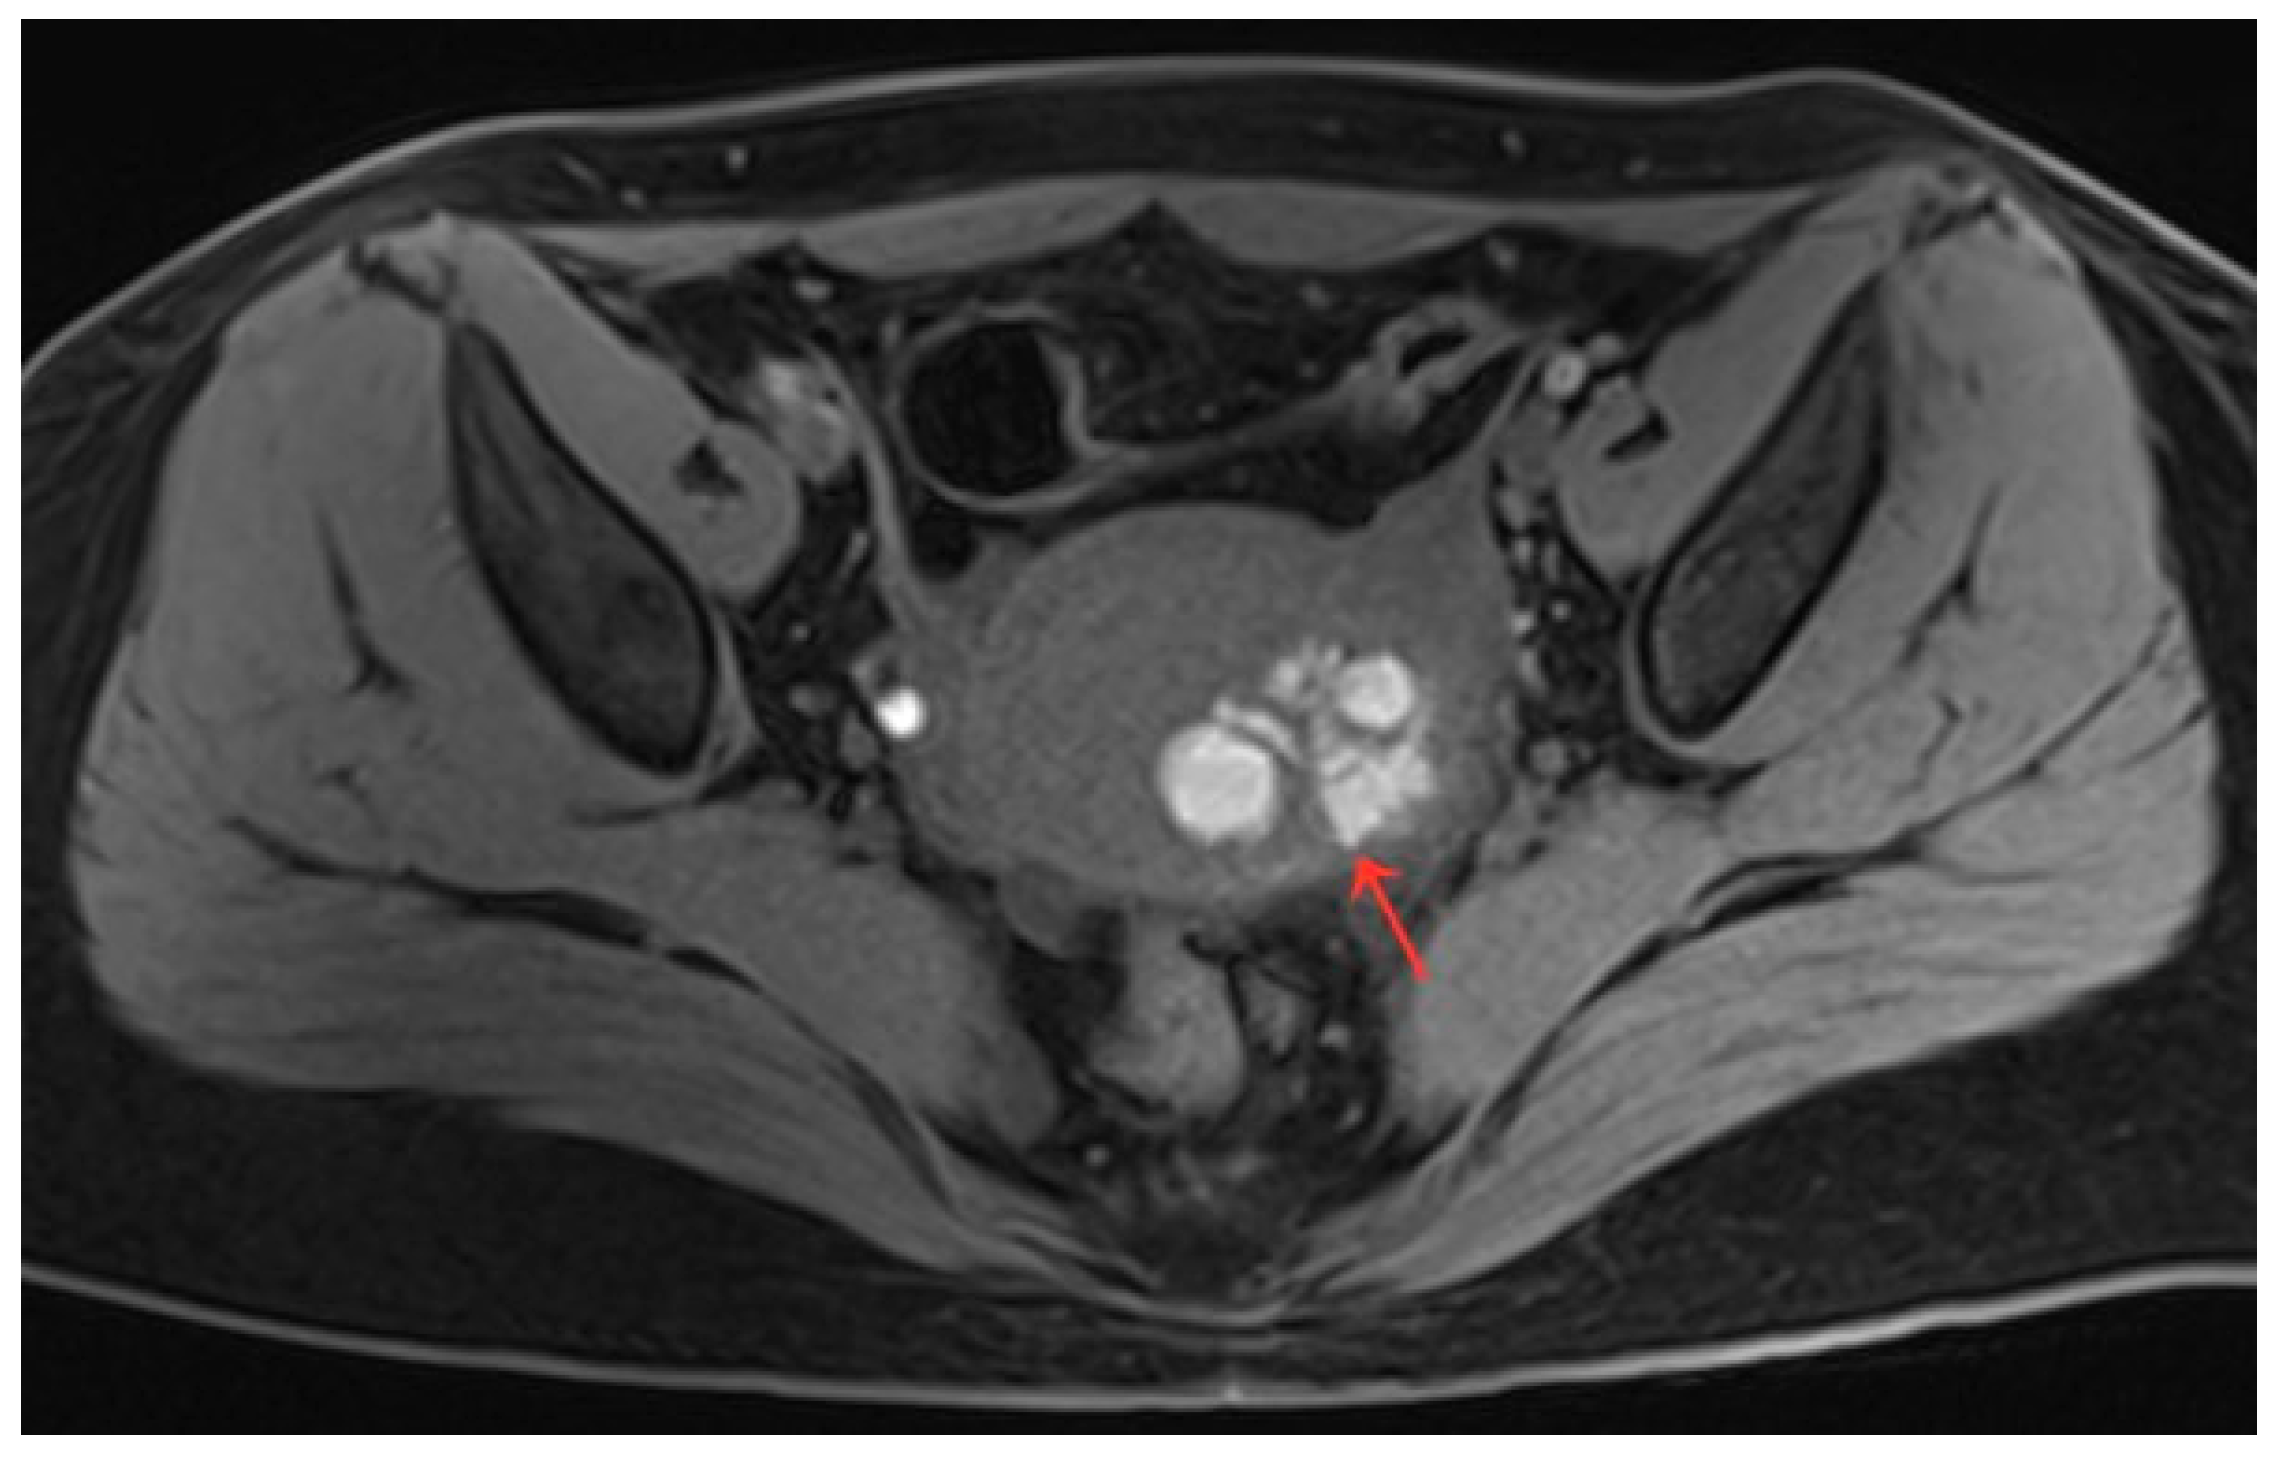

Figure 2.

Ultrasound image of the lesion before HIFU treatment (a). Ultrasonography after HIFU treatment shows no perfusion of the lesion (b).